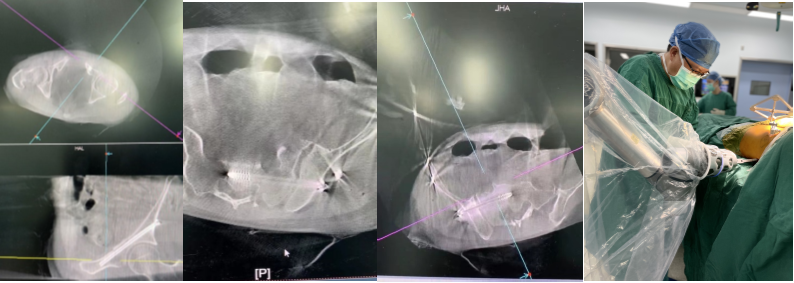

手术当天,骨科治疗组组长何罕亮副主任医师带领团队采用先进的二代臂机对患者进行骨盆图像采集,并将影像学资料上传至机器人计算机中。经过机器人的精密运算,患者的骨折三维图像非常直观地呈现在医生面前。随后,何主任团队根据图像实时进行手术规划,选择最佳置钉通道。手术机器人机械臂根据制定好的路线精准定位,将误差控制在1mm之内,使得医生不必扩大切口即可暴露骨折断端。只需3个毫米级切口,螺钉便可精准打入狭长的耻骨中,避免损伤重要的血管、神经组织。通道确定后,整个置钉过程短短几分钟便完成了,手术出血量不足10ml。精准的置钉操作使得医生不必担心反复调整所致的钉道松动,术后透视也进一步确认了螺钉位置准确无误,这预示着手术圆满成功。

机械臂手术现场